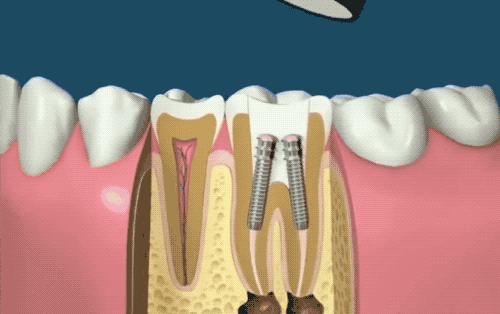

打入桩体

根管封闭后,如果牙体缺损过多(比如我这种少了半颗牙的情况),有时候也会放入一个或多个桩,就是下图这种医用螺丝,以增加牙齿的稳固性...